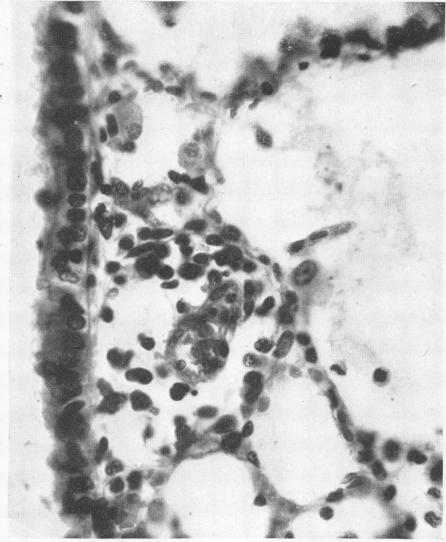

Manganese pneumonitis; further clinical and experimental observations.

Br J Ind Med. 1949 Apr;6(2):82-90. doi: 10.1136/oem.6.2.82.